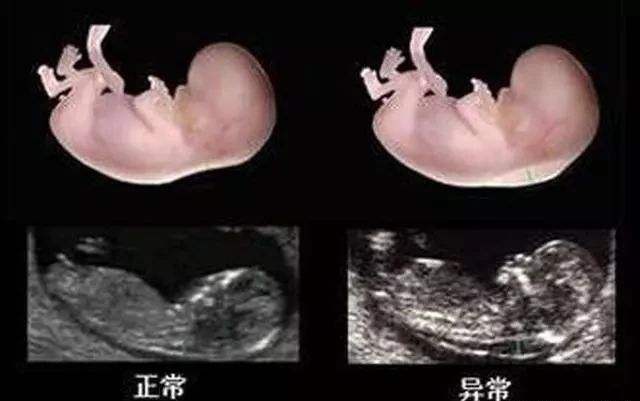

这次产检中做B超主要是做“排畸检查”,现在不少医院是直接做四维彩超。

对于四维彩超孕妈们并不陌生,可以完整的对胎儿的发育情况进行成像,能准确的检测出胎儿的头面部、骨骼、内脏和神经系统的异常,但是有些异常如先天性白内障等是无法检查出来的。